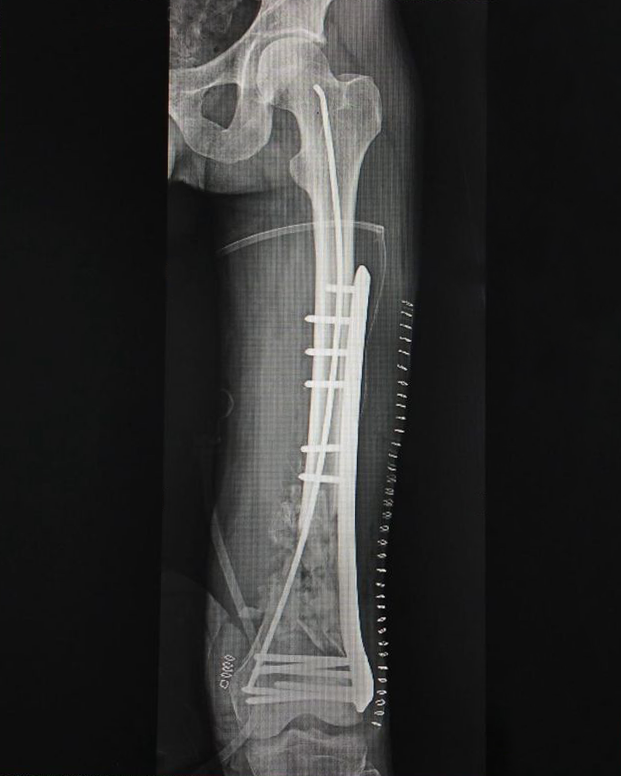

- Fracture Treatment: We specialize in the surgical and non-surgical treatment of

fractures, utilizing advanced techniques to ensure optimal healing and recovery.

- Expertise in Trauma Care: Dr. Zambare is highly skilled in managing complex trauma

cases, including multi-limb injuries and severe fractures. His expertise ensures that patients receive

precise and effective treatment for their injuries.

- Innovative Surgical Techniques: Under Dr. Zambare's leadership, our team employs the

latest surgical techniques and technologies to enhance patient outcomes. This includes minimally invasive

procedures that reduce recovery times and improve overall results.

- Imaging and Diagnostic Services: We offer comprehensive imaging and diagnostic

services, including high-resolution X-rays and orthoscannograms, to accurately diagnose and plan

treatment for orthopaedic conditions.